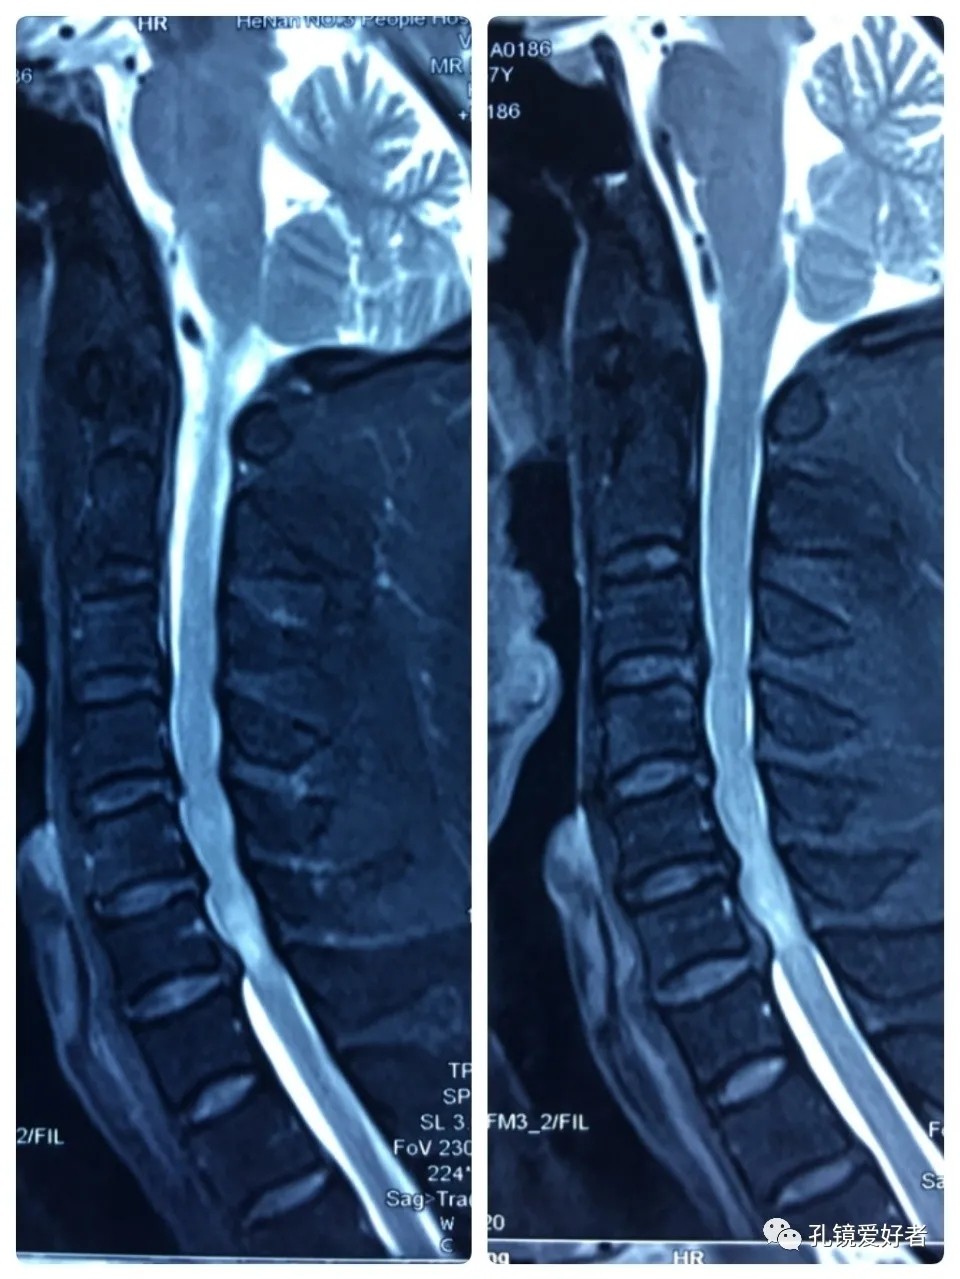

MRI - Sagittal Position

Plain MRI Scan

The patient's preoperative imaging data

The MRI shows that the cervical stenosis is on C3-4, C5-6 and C6-7. Considering the patient's clinical symptoms, C5-6 and C6-7 are the main affected segments. So it’s advised that the patient  undergo posterior cervical open-door laminoplasty. According to the patient, he had visited many hospitals before and received similar proposals of diagnosis and treatment- posterior cervical open-door laminoplasty. The reason he came to our hospital was that he wanted his surgery could be performed in a minimally invasive way. After considerable preoperative discussion with my colleagues and the patient, we decided to perform the minimally invasive endoscopic decompression for C5-6 and C6-7 double-segment stenosis through posterior approach (with the Delta system).